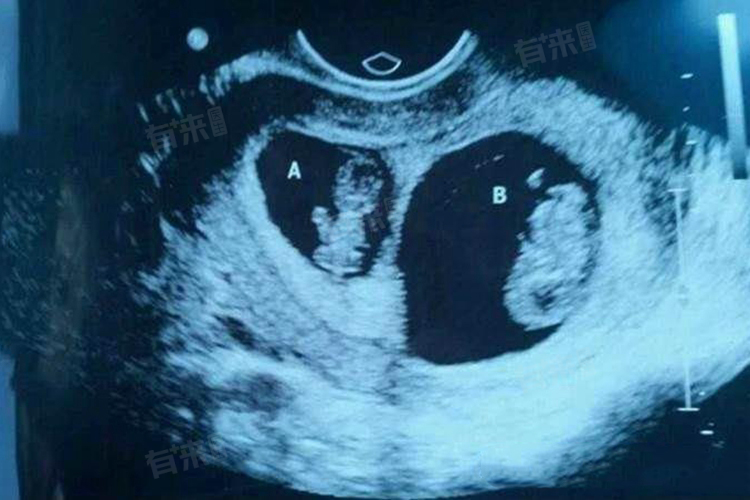

1、形成方式不同:同卵双胞胎是由一个受精卵分裂而成的两个胚胎,这意味着它们拥有相同的遗传物质。异卵双胞胎则是由两个不同的卵子分别受精形成的两个胚胎,每个胚胎都有各自独立的遗传物质。

6、受精过程不同:同卵双胞胎的形成是在精后早期,一个受精卵分裂成两个胚胎,异卵双胞胎的形成则涉及两个独立的卵子在同一月经周期内同时受精。